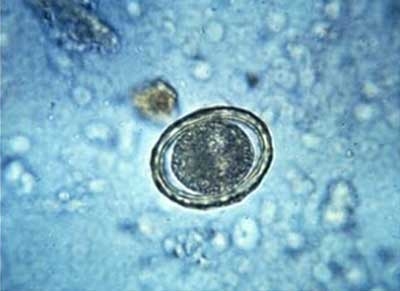

“一开始就使用驱虫药,反而会造成有些患者的病情加重。”孟强说,囊虫最常见的寄生部位是皮下组织、肌肉、大脑、眼球后方。对于感染了囊虫的患者来说,一般可以使用驱虫药物进行治疗。但在用驱虫药之前,要先使用一些脱水药物和激素?!俺嫣迨粲谝熘值鞍?,虫体死亡,大量蛋白质会使身体出现炎症反应或严重过敏反应等症状?!?孟强解释说,对于严重的寄生虫感染,一开始通常要使用小剂量的杀虫药,以免加重病情。

同时,孟强还告诉记者,像婷婷这么严重的囊虫感染,虽然可以通过分阶段的驱虫治疗将体内的囊虫杀死,但除了寄生在肠道内的囊虫,死后可以随粪便排出外,身体其他部位的寄生虫是无法排出的,或许还有后遗症的发生?!凹纳嬖谀圆坑跋熳畲螅嵊跋熘惺嗌窬低?,最常见的有癫痫,还有可能会造成智力下降,个别患者还会出现肢体瘫痪、语言功能障碍、感觉障碍等?!?/p>